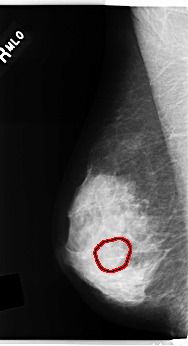

C_0284_1.RIGHT_MLO

RIGHT_MLO LINES 4840 PIXELS_PER_LINE 2632 BITS_PER_PIXEL 12 RESOLUTION 50 OVERLAY

FILE: C_0284_1.RIGHT_MLO.OVERLAY

TOTAL_ABNORMALITIES 1

ABNORMALITY 1

LESION_TYPE MASS SHAPE OVAL MARGINS OBSCURED

ASSESSMENT 3

SUBTLETY 4

PATHOLOGY BENIGN

TOTAL_OUTLINES 1

BOUNDARY